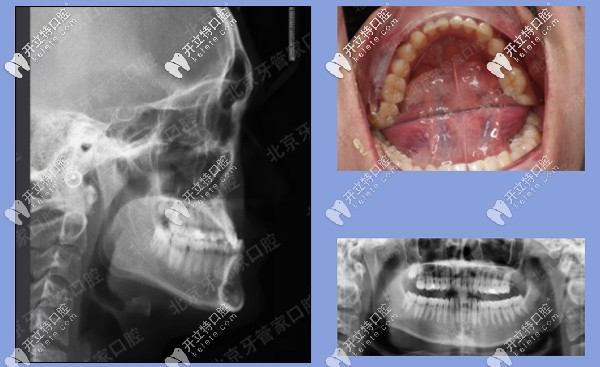

前期檢查:反合(又稱地包天),骨性三類(lèi),磨牙關(guān)系三類(lèi)。下前牙已經(jīng)發(fā)生舌傾,存在縫隙。

患者牙齒前期檢查

治療方案:內(nèi)收下牙列,上頜唇傾前牙,代償性掩飾治療。

矯治器:金屬固定矯正